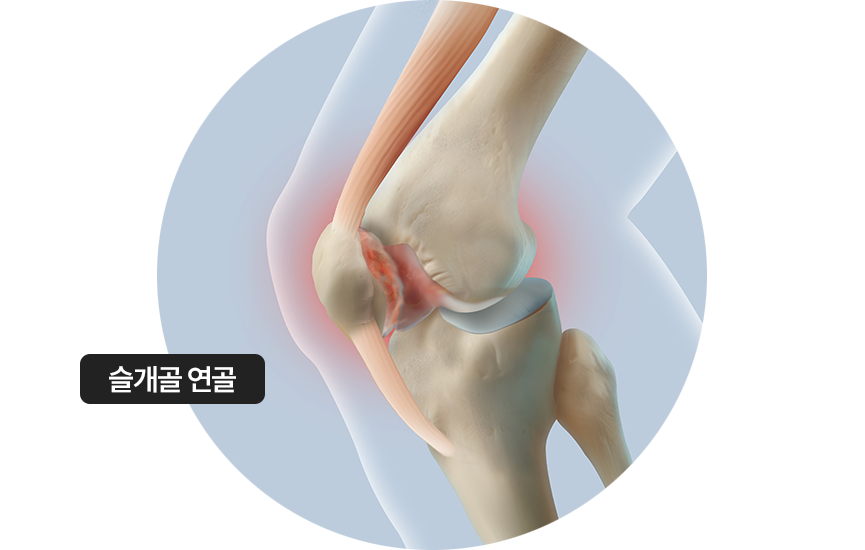

무릎 앞쪽 뼈인 슬개골을 보호하는 연골이 물렁하게 약화되어 시큰거리는 통증,

뻑뻑한 느낌, 저림 등의 증상 발생

주로 외상의 충격, 무릎관절의 지속적 자극 원인